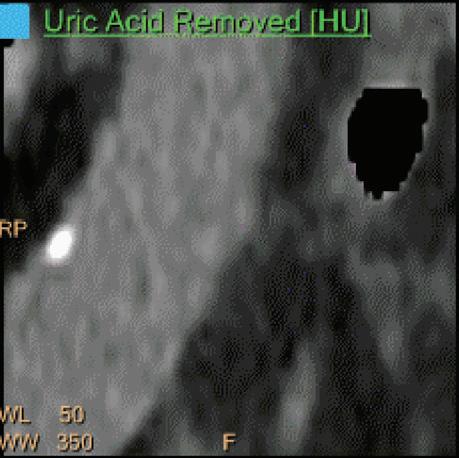

Uric Acid Removed [HU]

Voxels which are classified as not including uric acid (UA) show the corresponding HU of the reference Monoenergetic 70 keV CT image. Other voxels appear black. This image is useful to identify calcified stones and separate them from uric acid stones. UA and UA removed images are complementary to each other and are intended for uric acid/calcium classification. Pure soft tissues appear as part of the UA removed images (Figure 6).

Double oblique MPR image shows a calcified lesion and a uric acid stone side by side. The lower row displays spectral results in the Magic Glass, from left to right: conventional CT image, uric acid removed image, uric acid image, and Z effective map image. A comparative measurement on the conventional image shows that it is not possible to differentiate between them based on HU measurements (Calcified: 326.2 HU; UA stone: 329.4 HU). The Z effective map shows a large difference between the lesions (Calcified: 10.0; UA stone: 7.0) which enables us to classify them correctly.